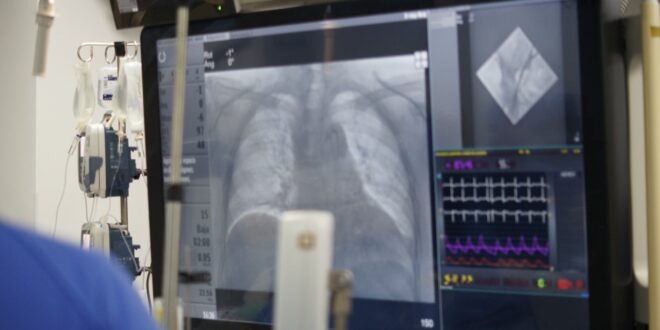

Culiacán, Sinaloa, martes 28 diciembre de 2021.- Gracias a la intervención de todo un equipo multidisciplinario altamente especializado del Hospital General Regional (HGR) No. 1 del Instituto Mexicano del Seguro Social (IMSS) en Culiacán, Sinaloa, se comenzó a aplicar la técnica conocida como Implante Percutáneo de Prótesis Aórtica o TAVI (por sus siglas en inglés), informó el médico José Luis Triano Doroteo.

El cardiólogo intervencionista adscrito al nosocomio señaló que este procedimiento, que se realiza en unidades hospitalarias de Tercer Nivel de Atención, es mínimamente invasivo y favorece la rápida recuperación de pacientes que anteriormente sólo tenían la opción de someterse a cirugías de corazón abierto.

“A los pacientes que requerían de este tipo de implantes antes sólo se les podía ofrecer la solución de una cirugía de corazón abierto. Estamos hablando de pacientes de 70, 80 o más años, en los que una cirugía era de muy alto riesgo. Este procedimiento es abismalmente diferente, pues se coloca la válvula a través de una punción y un catéter, llegamos hasta el corazón e inmediatamente esa válvula comienza a funcionar”, comentó Triano Doroteo.

Con este procedimiento, el médico explicó, se reducen en gran medida los tempos de estancia hospitalaria, pues al ser mínimamente invasivo sólo se deja al paciente un lapso de 24 horas para vigilancia de posibles arritmias en terapia intensiva posterior a la intervención, y después de ello, si así lo amerita, se puede dar de alta.

El médico especialista mencionó que para realizar este procedimiento se requiere una sala de hemodinamia y gracias a que el HGR No. 1 cuenta con esta infraestructura desde hace tres años, se pueden realizar ésta y otras técnicas de alta especialidad.

Finalmente, Triano Doroteo indicó que en la intervención participa todo un equipo multidisciplinario integrado por un cardiólogo intervencionista, un anestesiólogo, un cirujano cardiovascular, un cardiólogo clínico, el ecocardiografista, personal de Enfermería y técnicos radiólogos, entre otros elementos humanos.